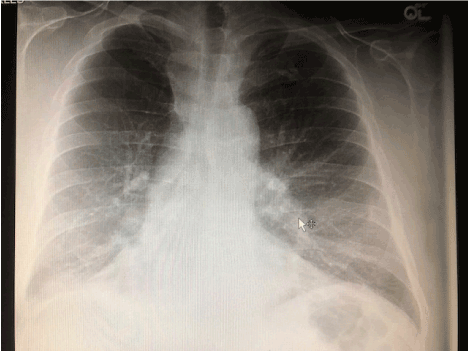

A chest x-ray showed an indistinct right basilar density with a potential small effusion possibly related to atelectasis or pneumonia (Figures 1A and 1B). There were no evident rib fractures.  While preparing for a chest CT, the patient coughed, and the bulge recurred.  CT images showed a large herniation of the right lower lobe between the 9th and 10th rib interspace. The adjacent ribs were separated with interruption of the associated intercostal muscles (Figures 2A and 2B, Figure 3 and Figure 4).

Figure 1A.  Admission chest X-ray, PA view showing a vague increased right basilar density thought to be a potential small effusion perhaps related to atelectasis or pneumonia.